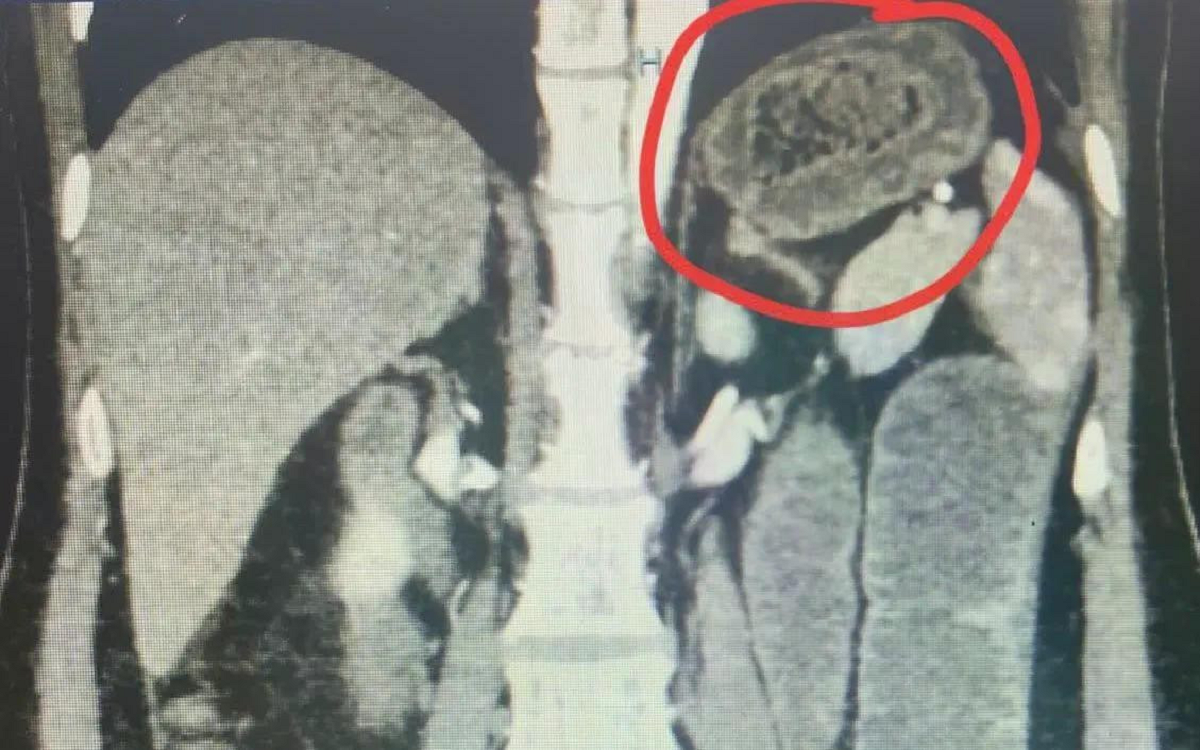

Kết quả chụp CT phát hiện dị vật kích thước khoảng 5x6mm nằm trong phế quản gốc trái, cách carina 6mm, bít kín hoàn toàn lòng phế quản. Trường phổi trái giảm thể tích, đông đặc toàn bộ – dấu hiệu xẹp hoàn toàn phổi trái do dị vật đường thở.